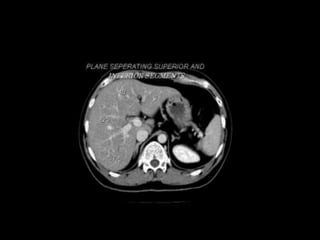

Right hepatic vein divides the right lobe into anterior and posterior

segments.

Middle hepatic vein divides the liver into right and left lobes (or right

and left hemiliver).This plane runs from the inferior vena cava to the

gallbladder fossa.

The Falciform ligament divides the left lobe into a medial- segment IV

and a lateral part - segment II and III.

The portal vein divides the liver into upper and lower segments.

The left and right portal veins branch superiorly and inferiorly to project

into the center of each segment.